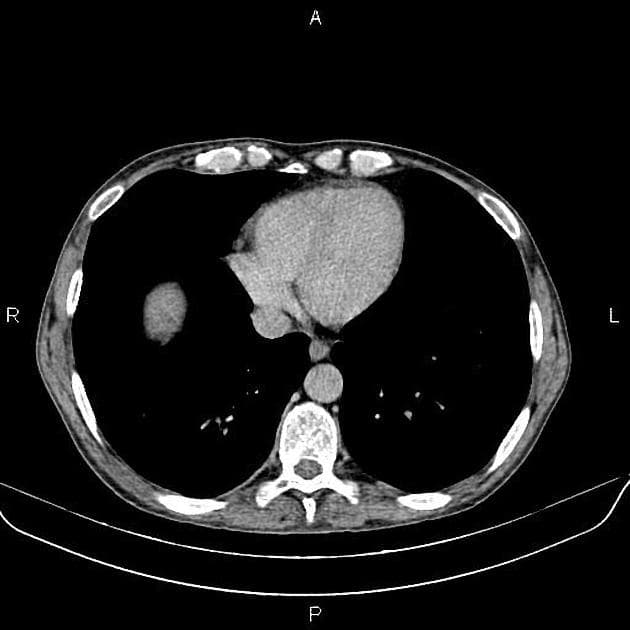

Chụp X-quang bụng không chuẩn bị (CT scanogram) cho thấy hình tăng tỷ trọng (metallic density) tại nửa bụng phải, cụ thể là ống nội soi dạng viên nang bị kẹt (trapped capsule endoscope). Hình ảnh này được xác nhận nằm trong lòng ruột (intraluminal), trong một quai hồi tràng.

Hình ảnh vệt thuốc cản quang barium rải rác thấy trong toàn bộ ống tiêu hóa chứa dịch, do bệnh nhân đã uống dung dịch barium loãng và Osmitrol trước khi làm MRI enterography.

Hình ảnh tăng quang (hyperenhancement) và thành ruột non dày lên tại nửa bụng phải, cũng như tại đại tràng trực – xích-ma.

Có hiện tượng giãn đoạn trước hẹp (prestenotic dilatation) hồi tràng và đại tràng trực – xích-ma, mức độ thay đổi.